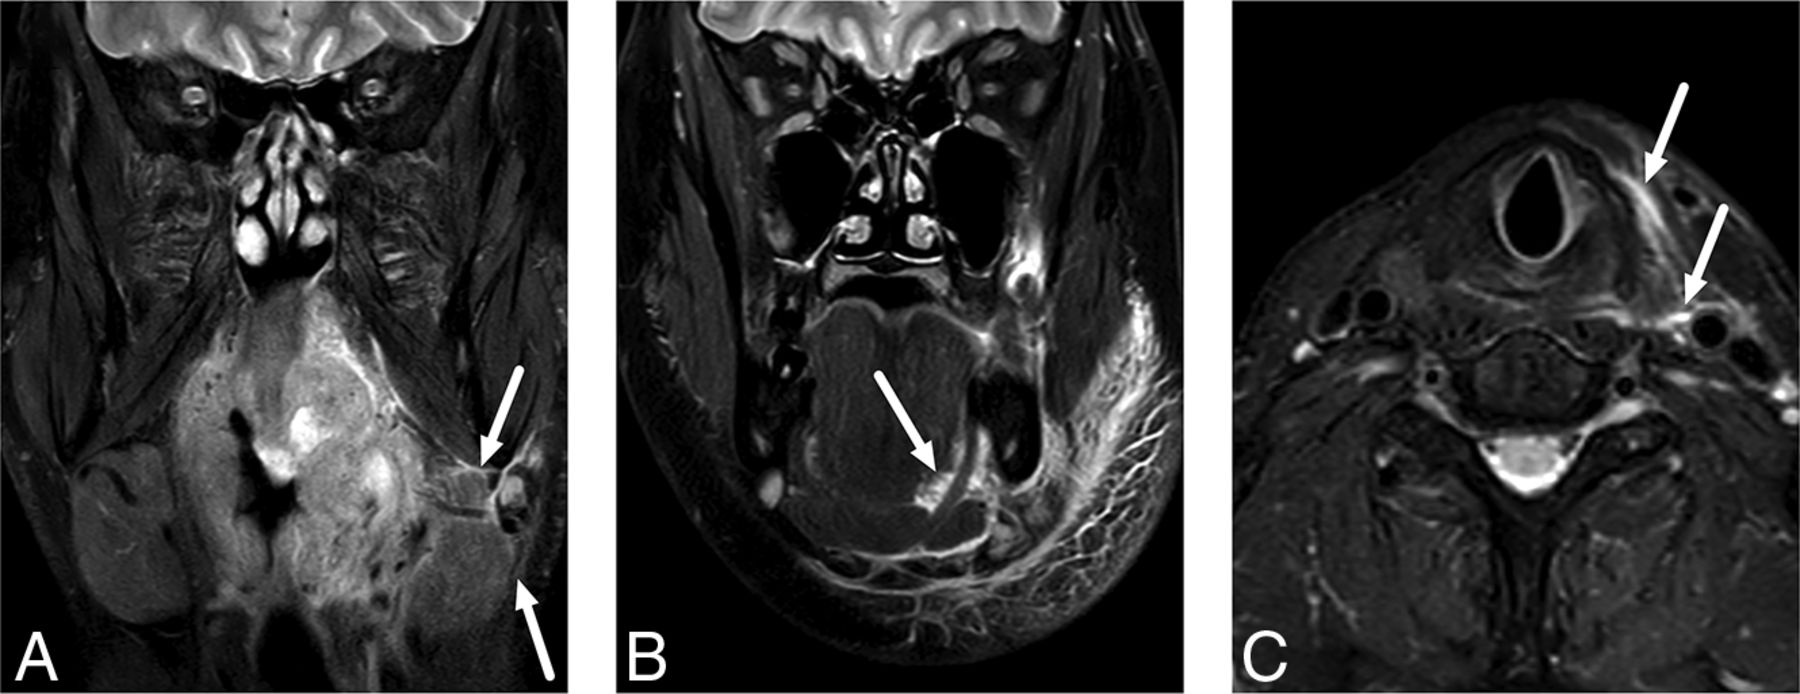

All patients had a final clinical diagnosis of tonsillar or pharyngeal infection. Of those with an abscess, 98 (89%) underwent an operation and an abscess was surgically confirmed in 96 patients, suggesting a PPV of 0.98. We had 2 patients with false-positive findings in whom no purulence was found. Six patients underwent an operation without MR imaging evidence of abscess; among these, 4 had true-negative findings and 2 had false-negative findings. Assuming 15 more patients with true-negative findings (ie, patients with a tonsillar infection but no abscess who recovered uneventfully following conservative treatment), we found a sensitivity, specificity, and accuracy of 0.98, 0.90, and 0.97, respectively, for an MR imaging diagnosis of an abscess (Table 2). In our experience, craniocaudal or lateral extension of an abscess far from the tonsil is the most reliable imaging sign of parapharyngeal or retropharyngeal extension (Fig 2). This morphologic assessment of deep extension had an overall sensitivity, specificity, and accuracy of 0.88, 0.90, and 0.89, respectively, as well as substantial agreement in the interobserver analysis (92% agreement, κ = 0.75).

Examples of uncomplicated PTA (A) and abscesses with deep extension (B–D) in different patients. In uncomplicated PTA, the abscess is retained within the pharyngeal constrictor muscle (A). In axial images, a deeply extending PTA is often lobulated and reaches laterally toward the parapharyngeal space, beyond the pharyngeal constrictor muscle (B). In sagittal images, a deeply extending PTA can reach far inferiorly (C) or superiorly (D) from the palatine tonsil (asterisk). The arrows denote abscesses.

The primary objective of emergency imaging is to provide a correct diagnosis and an anatomic basis for managing deep neck infections. Although PTAs do not typically require imaging, the patients in the current study underwent emergency MR imaging because either prior procedures had not yielded pus or a deep extension of the disease was primarily suspected. In our study of 98 patients with a radiologically diagnosed abscess who were later treated surgically, 96 had an abscess verified by the criterion standard. Of the false-positives, 1 patient had a hematoma after many puncture attempts. The second case was a very small abscess identified on MR imaging, and no purulence was identified during the operation. We found a sensitivity, specificity, and accuracy of 0.98, 0.90, and 0.97, respectively, for an MR imaging diagnosis of a pharyngotonsillar abscess. These results compare well with those of previous CT studies with the sensitivity, specificity, and accuracy of <0.90.4,10,11 Among the patients needing imaging for tonsillar infection, 37% had a deep extension to the parapharyngeal or retropharyngeal spaces. For the detection of parapharyngeal or retropharyngeal extension, the sensitivity, specificity, and accuracy were 0.88, 0.90, and 0.89, respectively, and interobserver agreement was substantial. In our experience, parapharyngeal or retropharyngeal extension should be suspected if the abscess reaches outside the palatine tonsil borders either laterally, superiorly, or inferiorly (Fig 2). Surgical literature shows that most cases of parapharyngeal abscesses are associated with concomitant PTA, suggesting that they are often direct extensions of PTA.12 Our current results indicate that deep extension can be detected or ruled out accurately by MR imaging.